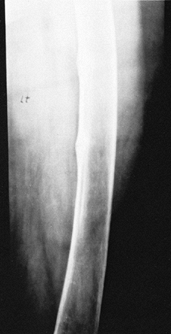

an indistinct zone of provisional calcification (Fig. 131.5).

Long-bone bowing, genu valgum or genu varum, and stress fractures (Looser’s lines) are also seen (Fig. 131.6).

Figure 131.5. Rickets: Notice the widened, cupped physes on the AP (A) and the lateral (B) radiographs.

Figure 131.6. Looser’s lines in osteomalacia.